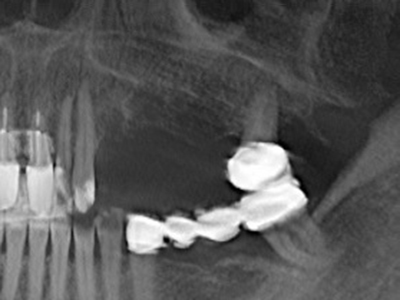

La preparación de la ventana lateral en la elevación del suelo del seno maxilar representa un enorme reto, sobre todo para profesionales de la implantalogía que tienen poca experiencia en técnicas quirúrgicas. Retirar la cobertura ósea del seno maxilar sin provocar daños en la membrana de Schneider es tan solo una parte de la operación; tras crear un acceso suficiente, es preciso movilizar con cuidado la mucosa del seno maxilar a fin de dejar espacio para el material o los implantes que vayan a incorporarse. En esta aplicación la cirugía piezoeléctrica resulta útil en dos sentidos: por un lado, el uso de insertos diamantados permite realizar una retirada selectiva del hueso y, si se actúa con cuidado, la membrana permanece intacta, y por otro lado, las frecuencias de ultrasonidos favorecen también un desprendimiento sin problemas de la membrana, pues se transfieren al espacio comprendido entre la mucosa y el suelo del seno maxilar gracias al uso de piezas romas especiales (Cassetta, Ricci et al. 2012, Pereira, Gealh et al. 2014) (Rickert, Vissink et al. 2013). De este modo, no es de extrañar los trabajos publicados en la actualidad sobre la técnica de elevación del suelo del seno maxilar mediante la técnica de Caldwell-Luc con instrumentos piezoeléctricos (Wallace, Tarnow et al. 2012).

En la extracción de bloques óseos la piezocirugía también presenta ventajas adicionales: Además de la alta precisión en la osteotomía que ya se ha descrito antes, se ha comprobado que el uso de los delgados insertos de sierra resulta especialmente cuidadosas con el hueso. Frente a esto, sobre todo cuando se usan las fresas de Lindemann, cabe esperar pérdidas en la extracción significativamente más altas debido al mayor grosor de la parte frontal del cabezal (Lakshmiganthan, Gokulanathan et al. 2012). La separación basal que se necesita en particular en los injertos de bloque extraídos de forma retromolar se ve facilitada mediante sierras perpendiculares especialmente previstas a tal fin, lo que permite considerar que la cirugía piezoeléctrica es un procedimiento preciso y seguro para la obtención de bloques de hueso en el área retromolar (Happe 2007) (fig. 1-12).